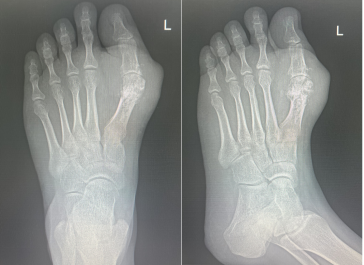

骨伤科二病区团队为其制定一期行双足针刀镜微创手术彻底清理痛风石:

一期微创手术清理术后

二期右足行3D打印个体化跖趾关节重建方案:通过CT获取足部三维数据,1:1还原骨骼缺损与畸形结构,数字化设计完全匹配患者解剖的定制假体,再通过金属3D打印技术制造专属假体,真正实现“量骨定制、精准植入”。